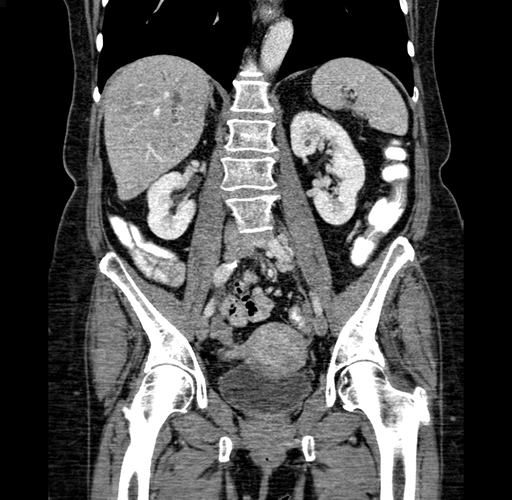

Pre-Chemo: Coronal Venous